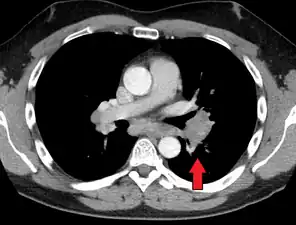

Hilar adenopathy especially on the person's left (coronal CT)

Hilar adenopathy especially on the person's left (transverse CT)